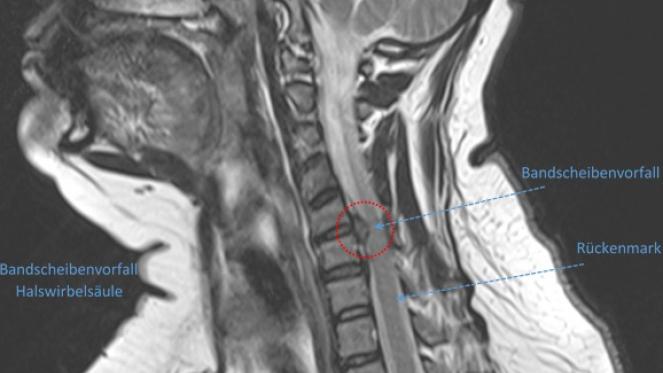

Bandscheibenvorfälle (NPP)

Bandscheiben sind flexible, faserknorpelige Verbindung, die als Stoßdämpfer zwischen den Wirbel dienen.

Mit zunehmendem Lebensalter kann es zu verschleißbedingten Rissen am äußeren Ring der Bandscheibe (Faserring) und zu einem Austritt des gallertartigen Kerns kommen. Dieser kann die benachbarten Nervenwurzeln oder das Rückenmark zusammendrücken und zu lokalen oder ausstrahlenden Schmerzen in den Armen und Beinen, ggf. auch mit Sensibilitätsstörungen und motorischen Ausfällen, führen.

bei Spinalkanalstenose - Halswirbelsäule (Bandscheibenvorfälle,